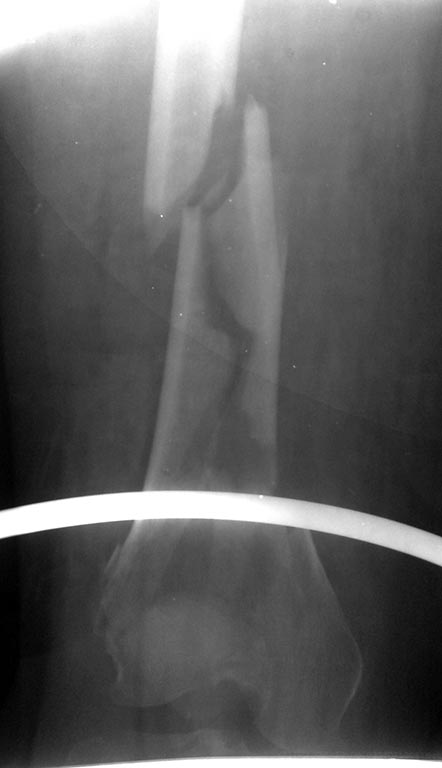

[Ortho] Перелом бедра

Планирую остеосинтез бедра пластиной. Есть ли у кого рекомендации по

доступу на данный явно внутрисуставной перелом. Может сноски на

видеоролики. Возможности КТ исследования нет.